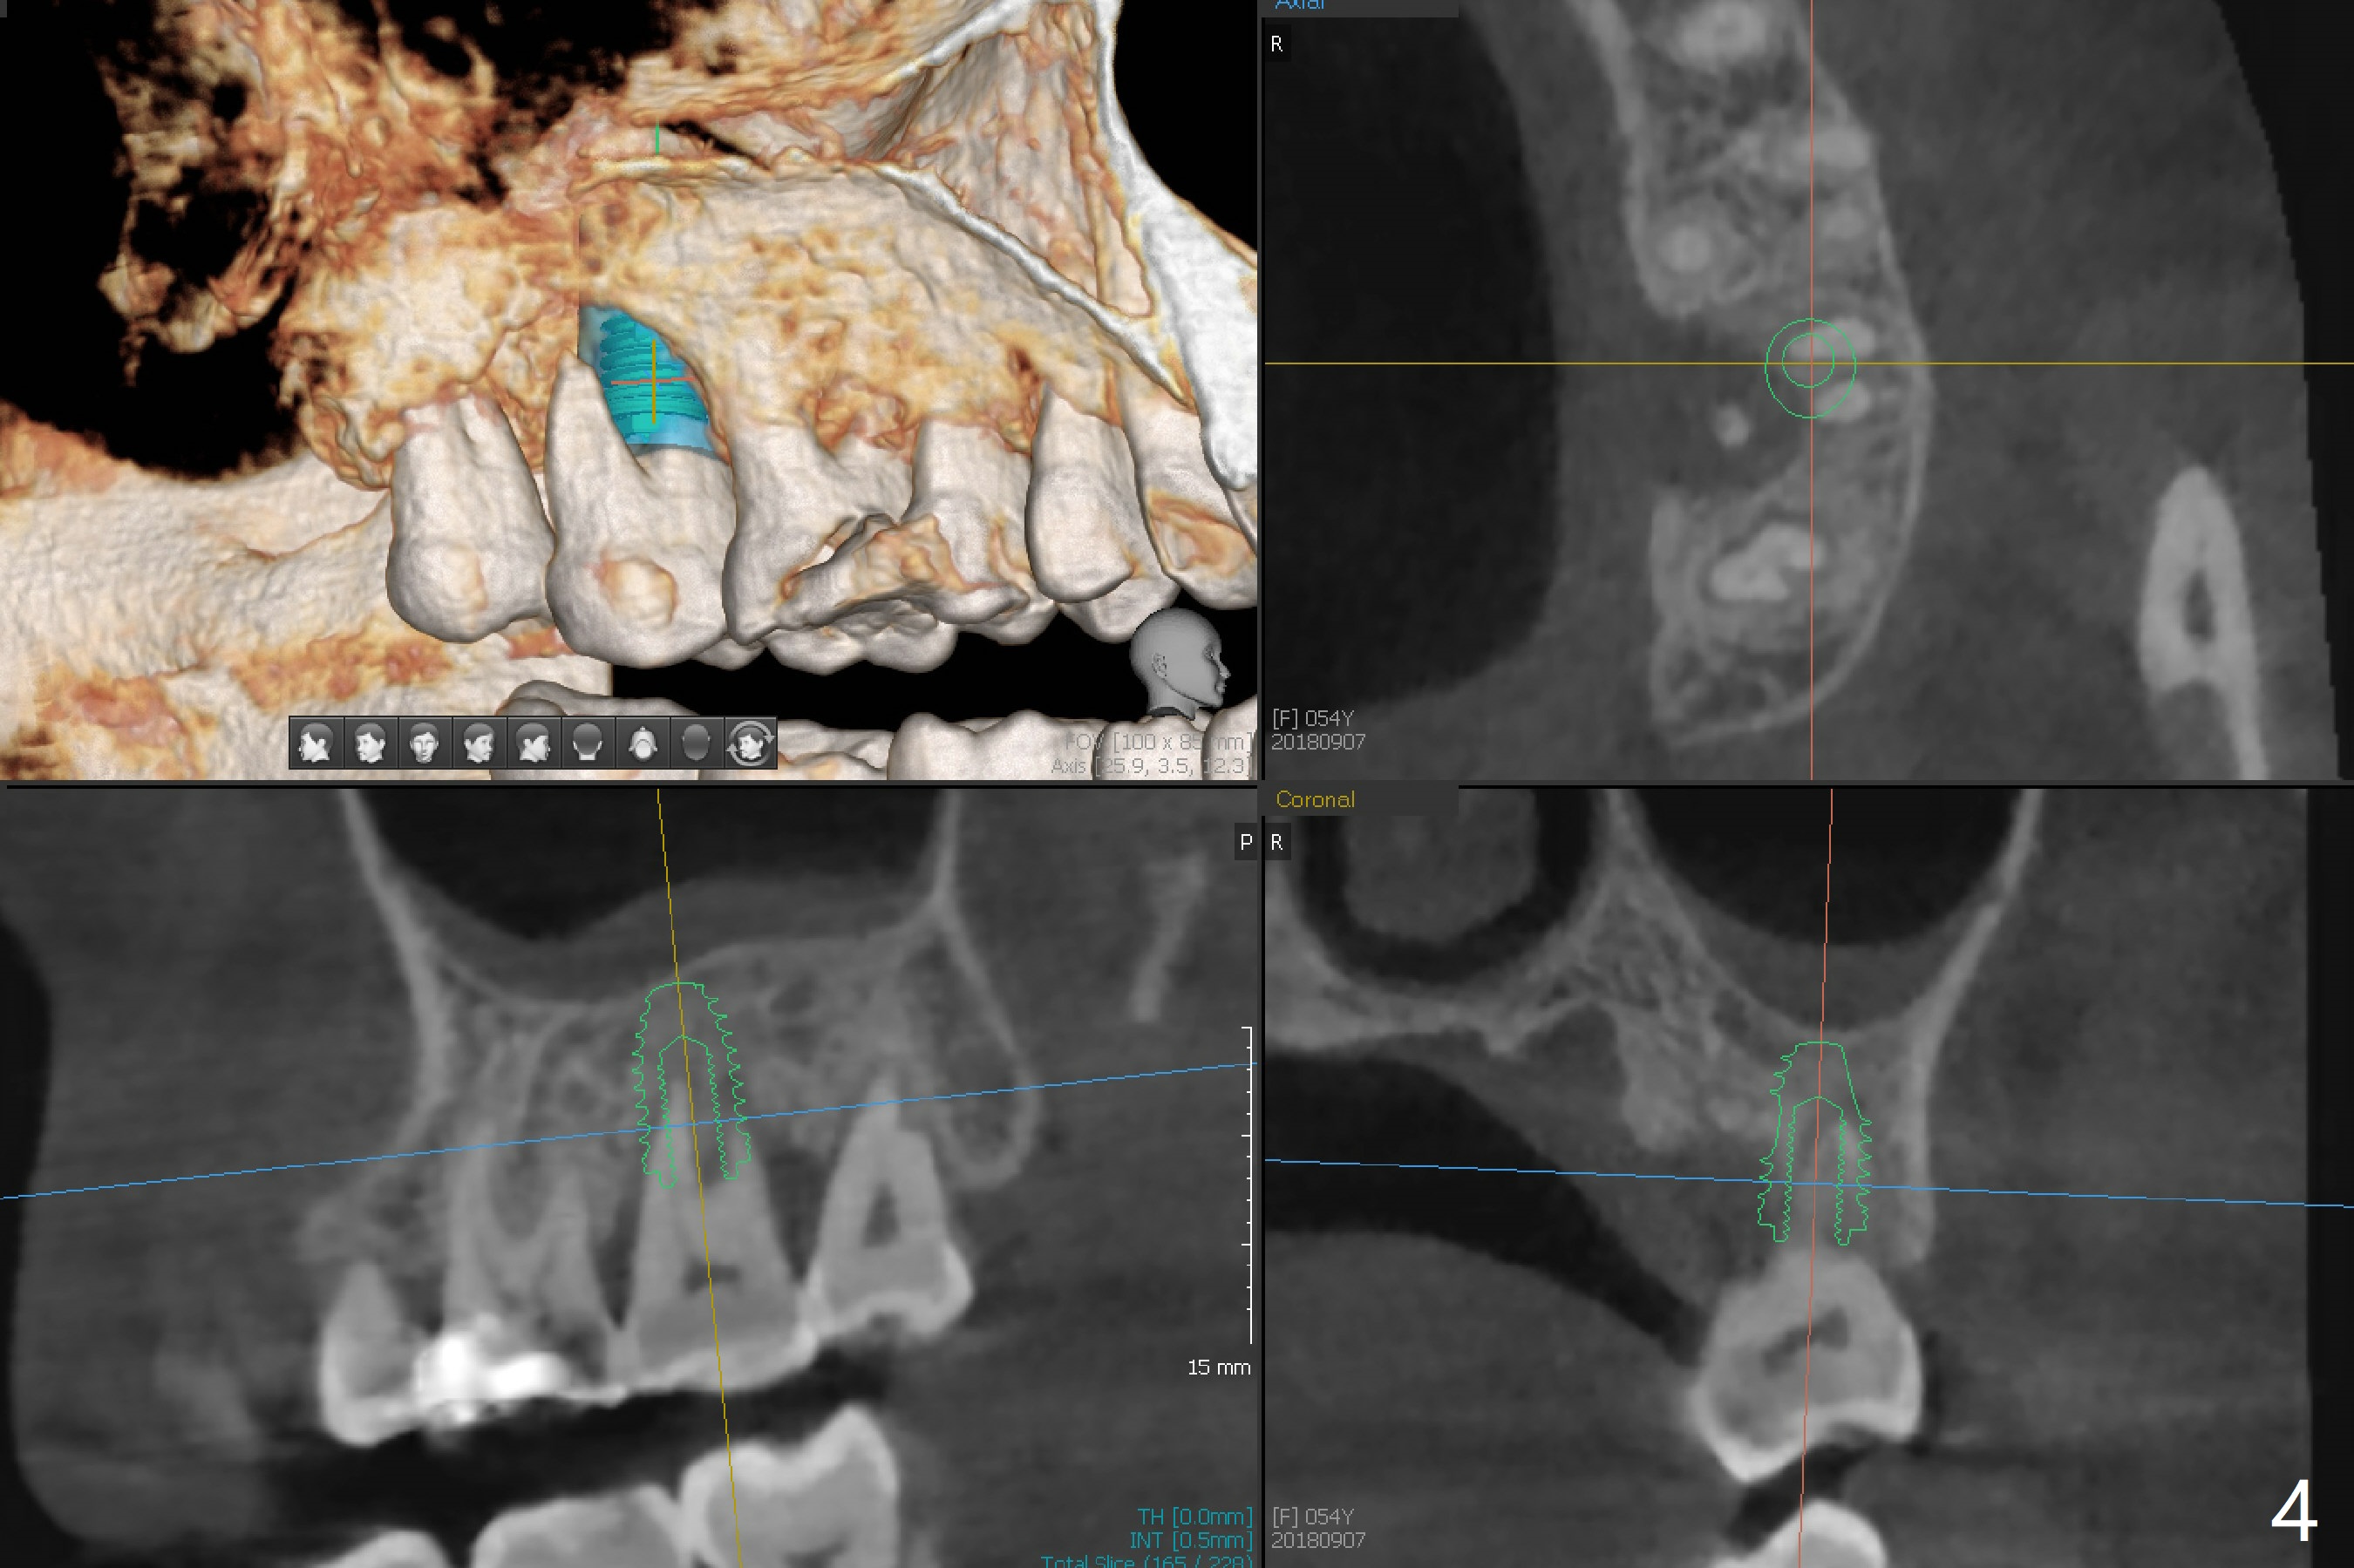

The 54-year-old woman (bruxer) agrees to have implant because of the loose tooth at #15 (Fig.1 (pan)). Since the left sinus membrane is thickened (Fig.2 *), an immediate implant will not be penetrated the sinus floor if primary stability is acceptable. If the sinus lift has to be done, PRF membrane/plug will be prepared. The large periradicular radiolucency is associated with the vertical palatal root fracture (Fig.3). A 5x8.5 mm implant is placed as buccal as possible with guide (Fig.4).